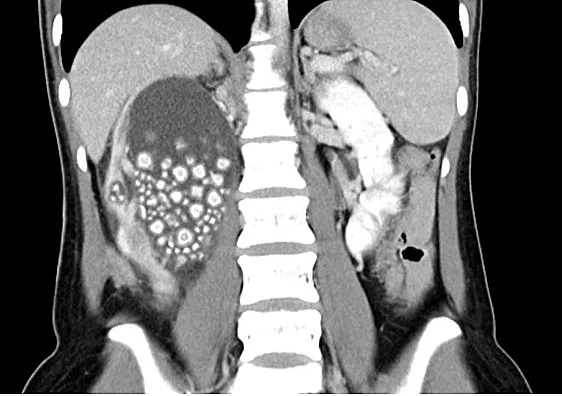

.שיאו צ'ו, צעירה בת 20 מטאיוואן, הרגישה כאבים עזים בגופה. במהלך בדיקה רפואית שלה התגלה כי הכליה הימנית שלה הייתה במצב קריטי כשהיא עמוסה בנוזל ועמוסה בצפיפות בכ-300 אבנים בכליות בגדול של 5 מ"מ ועד 2 ס"מ. מצבה של שיואו יו הסתבך עוד יותר בשל ספירת תאי דם לבנים גבוהה, מה שמעיד על זיהום.